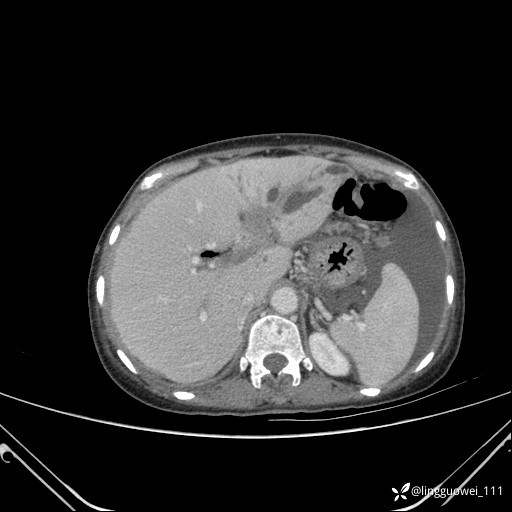

病例女,65岁,门诊行胃肠镜检查后,说腹胀入院检查,CT能发现病因吗?已公布结果

主诉:门诊行胃肠镜检查后,诉腹胀,入院检查,肝有病变吗?腹膜及腹腔的表现有特征性吗?

平扫:

增强动脉期:

门脉期:

延迟期: